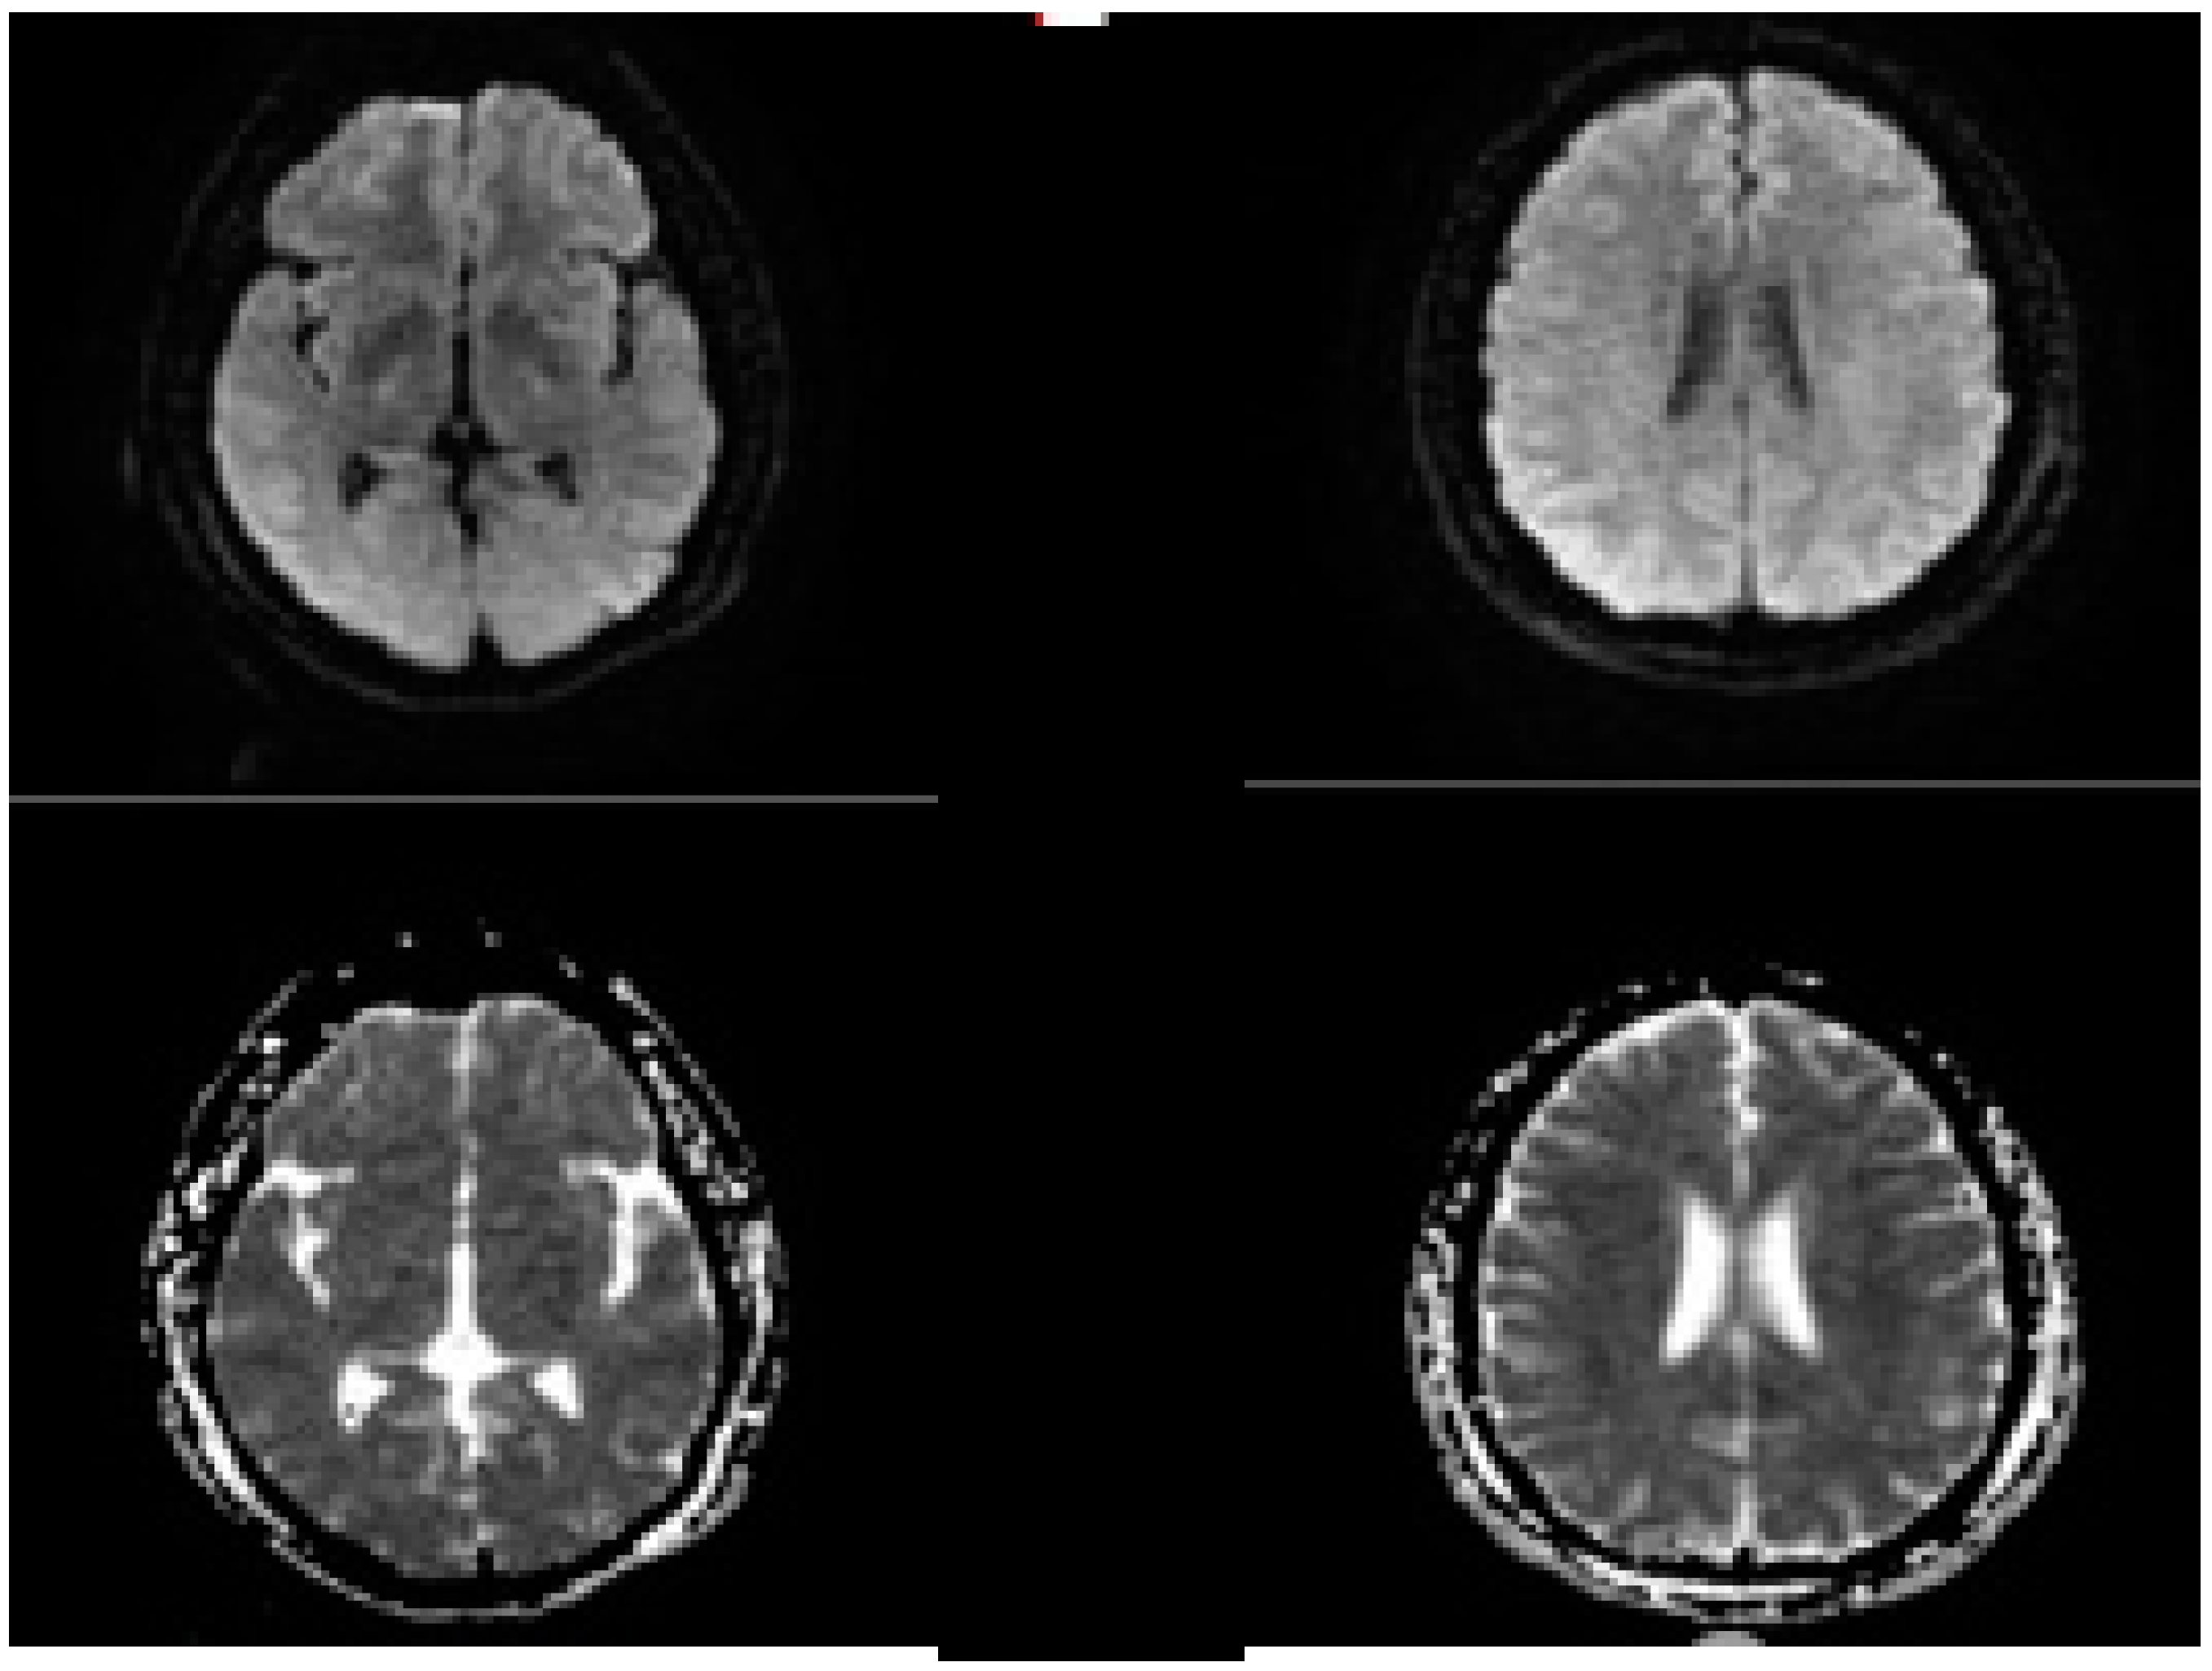

2.5. Evolution of the Concept of the Tissue Window and Late Window Trials

- Nogueira, R.G.; Jadhav, A.P.; Haussen, D.C.; Bonafe, A.; Budzik, R.F.; Bhuva, P.; Yavagal, D.R.; Ribo, M.; Cognard, C.; Hanel, R.A.; et al. Thrombectomy 6 to 24 Hours after Stroke with a Mismatch between Deficit and Infarct. N. Engl. J. Med. 2018, 378, 11–21. [Google Scholar] [CrossRef]

- Albers, G.W.; Marks, M.P.; Kemp, S.; Christensen, S.; Tsai, J.P.; Ortega-Gutierrez, S.; McTaggart, R.A.; Torbey, M.T.; Kim-Tenser, M.; Leslie-Mazwi, T.; et al. Thrombectomy for Stroke at 6 to 16 Hours with Selection by Perfusion Imaging. N. Engl. J. Med. 2018, 378, 708–718. [Google Scholar] [CrossRef]